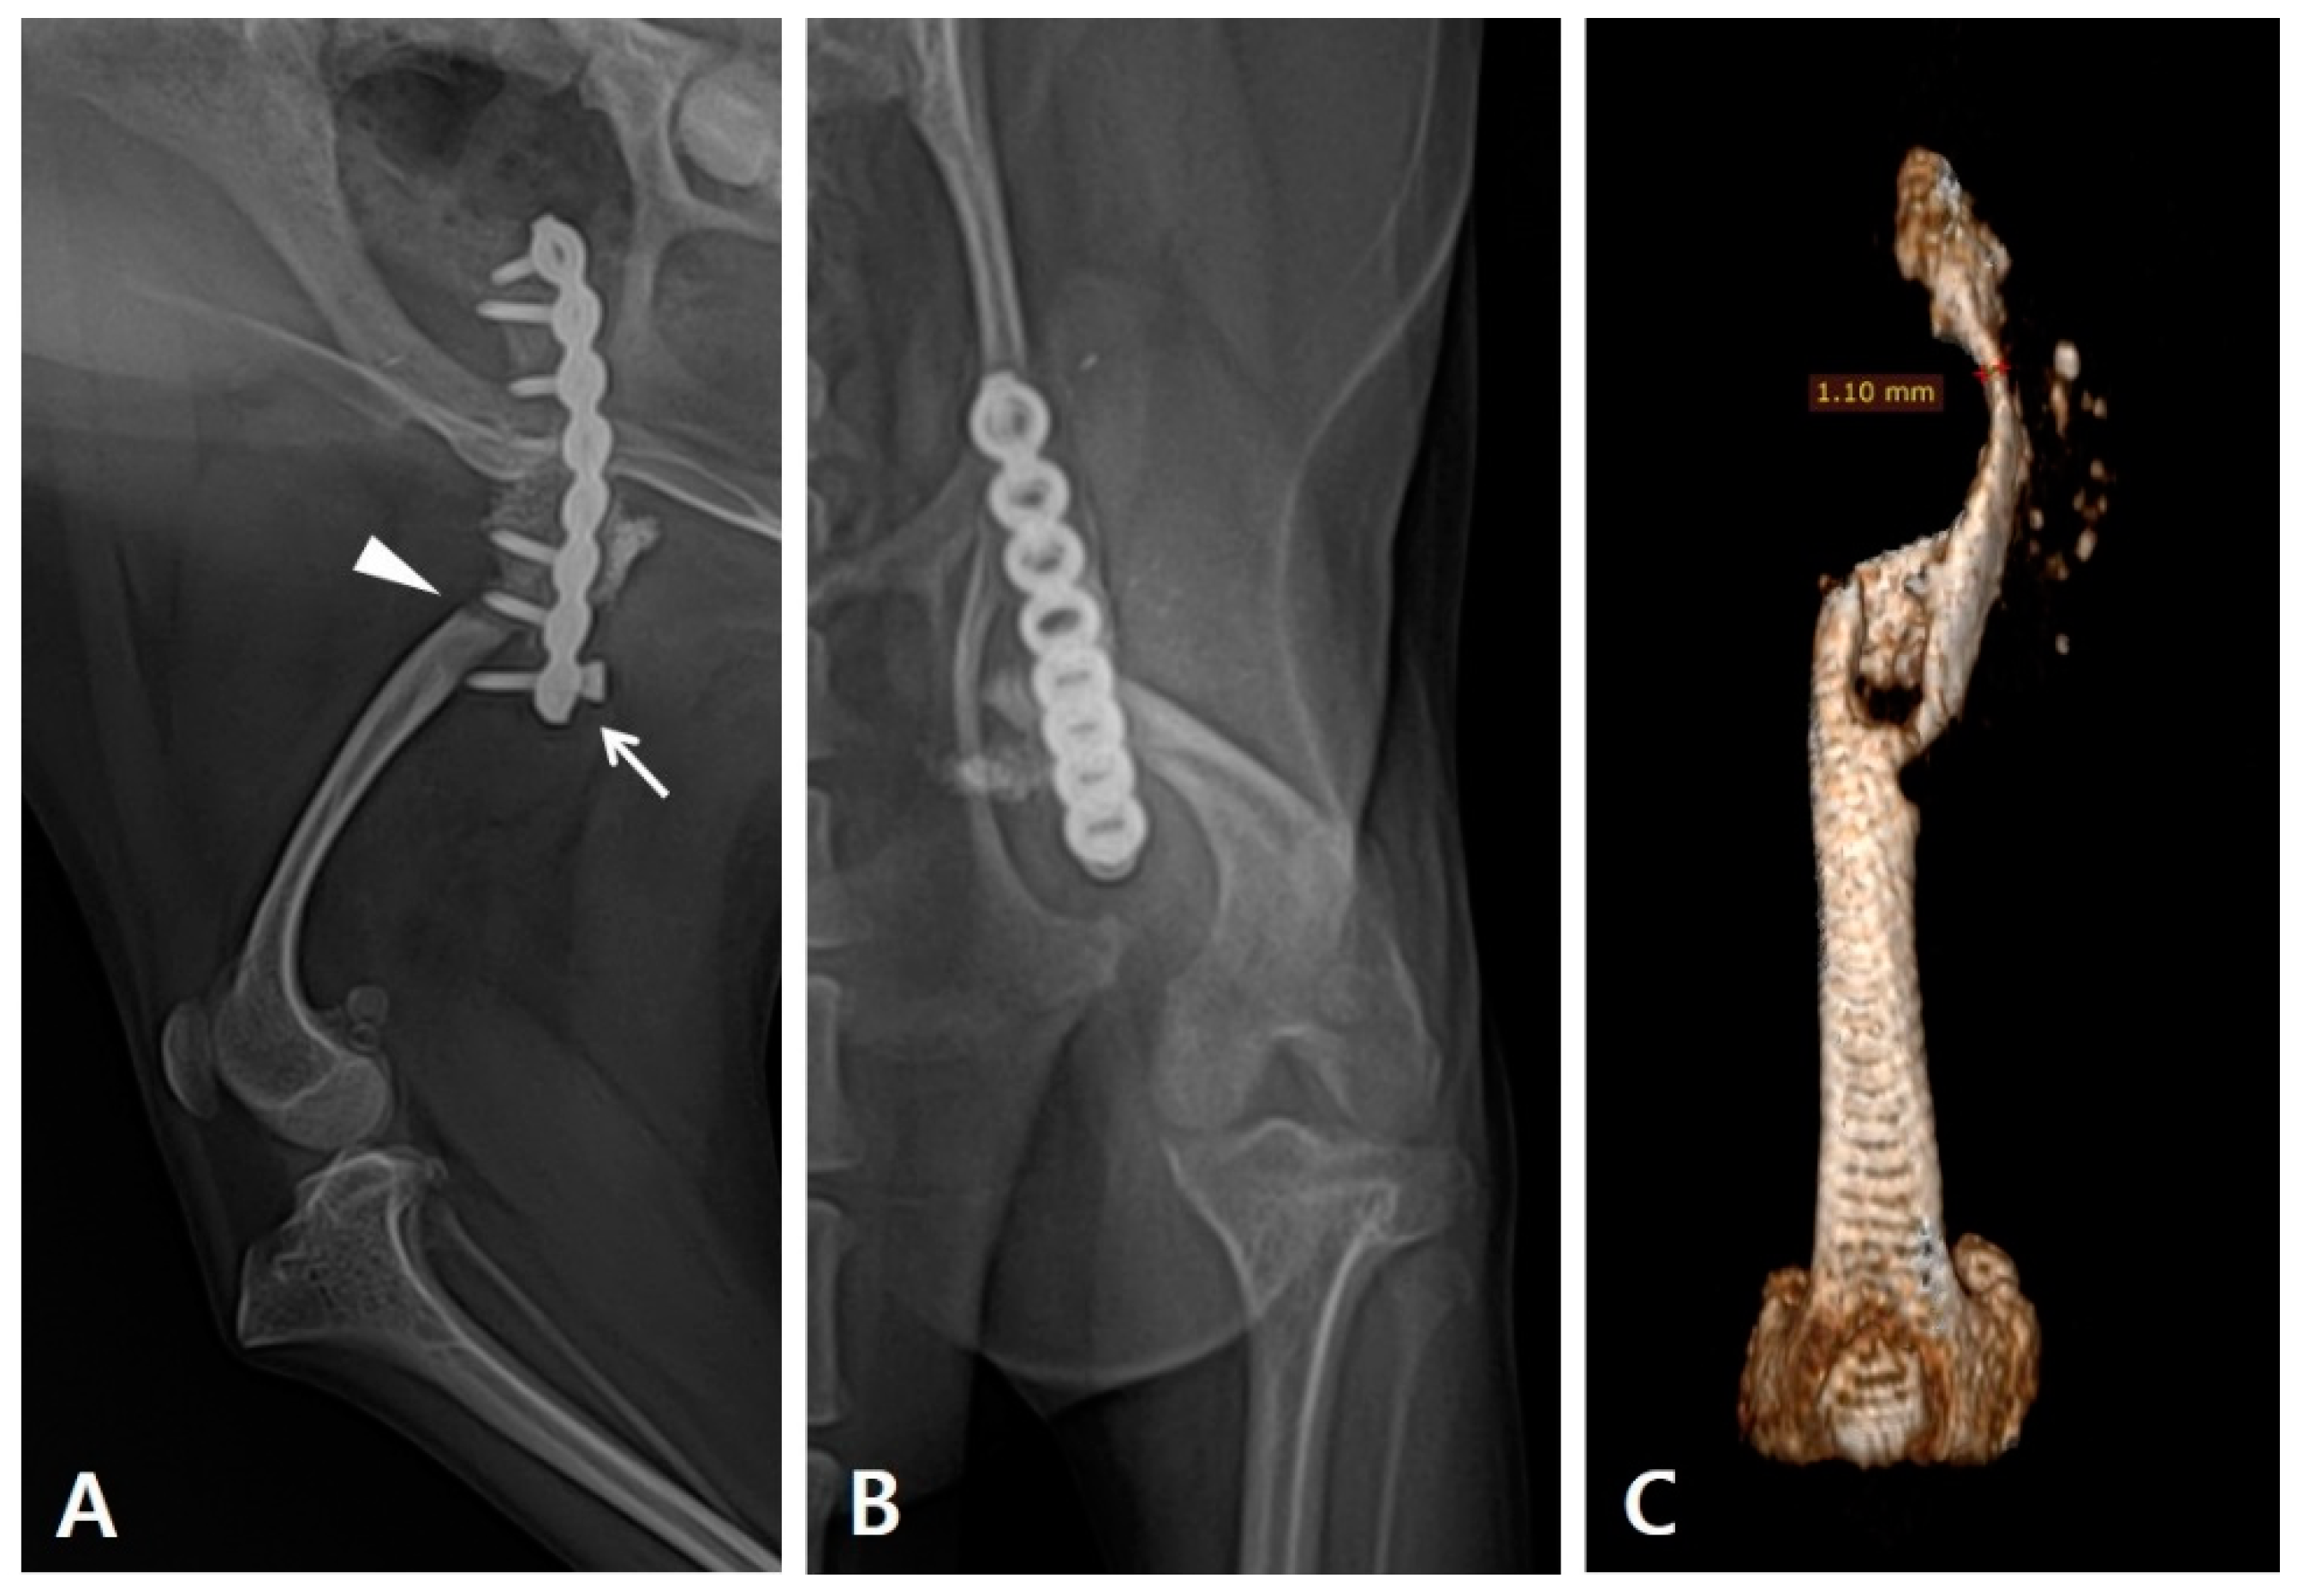

Figure 1. Preoperative evaluation and planning carried out using radiography and CT scans. (A) Lateral and (B) craniocaudal radiograph of the patient's left femur. Re-fracture occurred (arrowhead) with the distal most screw pulled out (arrow). Underdeveloped femur and tibia are observed. (C) The three-dimensional reconstructed CT image of the left femur after implant removal shows severe atrophy in the proximal bone fragment, with 1.10 mm thickness at its thinnest point.

During the physical examination, the range of motion of the stifle and hock joints was found to be severely decreased. Radiography revealed implant failure in the left femur, severe atrophy of the proximal bone fragment, and retardation of the ipsilateral distal bone fragment of the femur and tibia compared to the contralateral side. (Figure 1A). The failed implants were removed and computed tomography (CT) was performed for preoperative surgical planning (Figure 1B). An autogenous corticocancellous bone graft was planned and the coccygeal bone was ultimately chosen as the autograft (Figure 2).